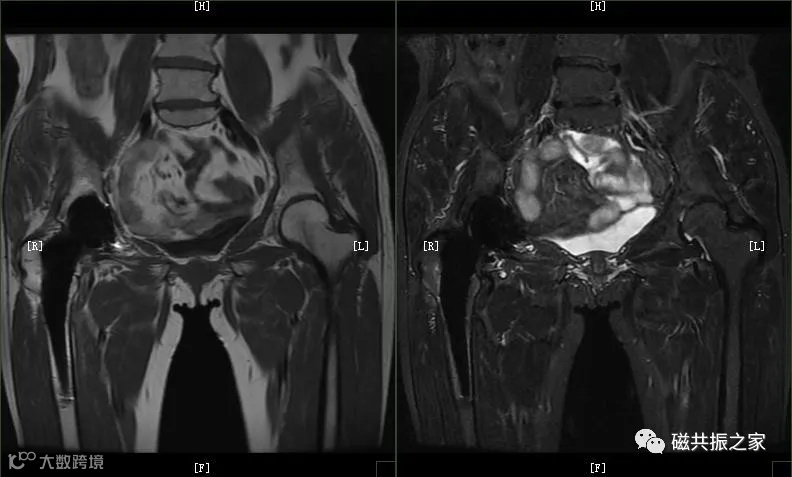

图像伪影干扰:金属材质可能引发局部信号丢失或几何畸变,影响心脏瓣膜及周边结构的成像质量。伪影范围通常局限于瓣膜周围的局部区域,如有必要进行该区域的MRI检查时,可通过序列优化(如增加带宽、使用金属伪影抑制技术)减轻影响。